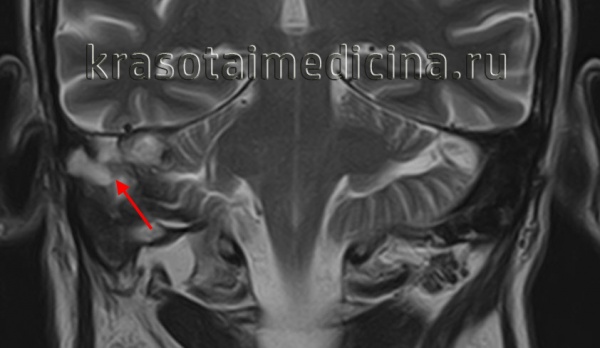

• Т2 ВИ:

о Тонкосрезовая МРТ Т2 высокого разрешения: отосклероз (даже распространенный) может не определяться

о В больших бляшках может обнаруживаться легкое повышение интенсивности сигнала

• Т1 ВИ С+:

о Контрастирующиеся точечные очаги в медиальной стенке среднего уха (ФОто) ± перикохлеарные очаги в костном лабиринте (КОто):

- Наиболее очевидны при сочетании ФОто и КОто

о В тяжелых случаях контрастирующиеся участки могут обнаруживаться повсюду в костном лабиринте

У некоторых пациентов с положительным симптомом Шварца и значительными спонгиотическим изменениями при КТ, МРТ с контрастированием обнаруживает усиление в очагах деминерализации. Эффект, по предварительному заключению, возникает в связи с накоплением контраста в кровеносных сосудах и лакунах, образованных активными спонгиозными очагами.